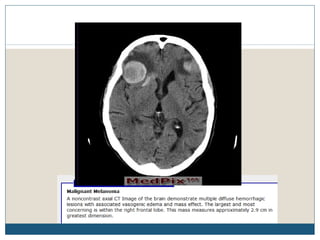

CÉREBRO

 A freqüência de metástases cerebrais é maior com melanoma do

que para a maioria das outras doenças malignas.

 Metástases no SNC são a segunda causa mais comum de

mortalidade.

 Na TC, metástases intracranianas podem aumentar uniformemente

ou em um padrão em forma de anel. Padrões similares são vistos em

RM.

 RM do cérebro é o procedimento de escolha para os sintomas

atribuíveis ao SNC, e é opcional para os pacientes assintomáticos

com estágio III ou IV da doença.

 A indicação para os exames de rotina do cérebro em pacientes

assintomáticos com doença loco-regional avançada é controversa.

Alguns especialistas defendem estudos para procurar envolvimento

do SNC apenas em pacientes sintomáticos.

CÉREBRO  A freqüênciade metástases cerebrais é maior com melanoma do que para a maioria das outras doenças malignas.  Metástases no SNC são a segunda causa mais comum de mortalidade.  Na TC, metástases intracranianas podem aumentar uniformemente ou em um padrão em forma de anel. Padrões similares são vistos em RM.  RM do cérebro é o procedimento de escolha para os sintomas atribuíveis ao SNC, e é opcional para os pacientes assintomáticos com estágio III ou IV da doença.  A indicação para os exames de rotina do cérebro em pacientes assintomáticos com doença loco-regional avançada é controversa. Alguns especialistas defendem estudos para procurar envolvimento do SNC apenas em pacientes sintomáticos.